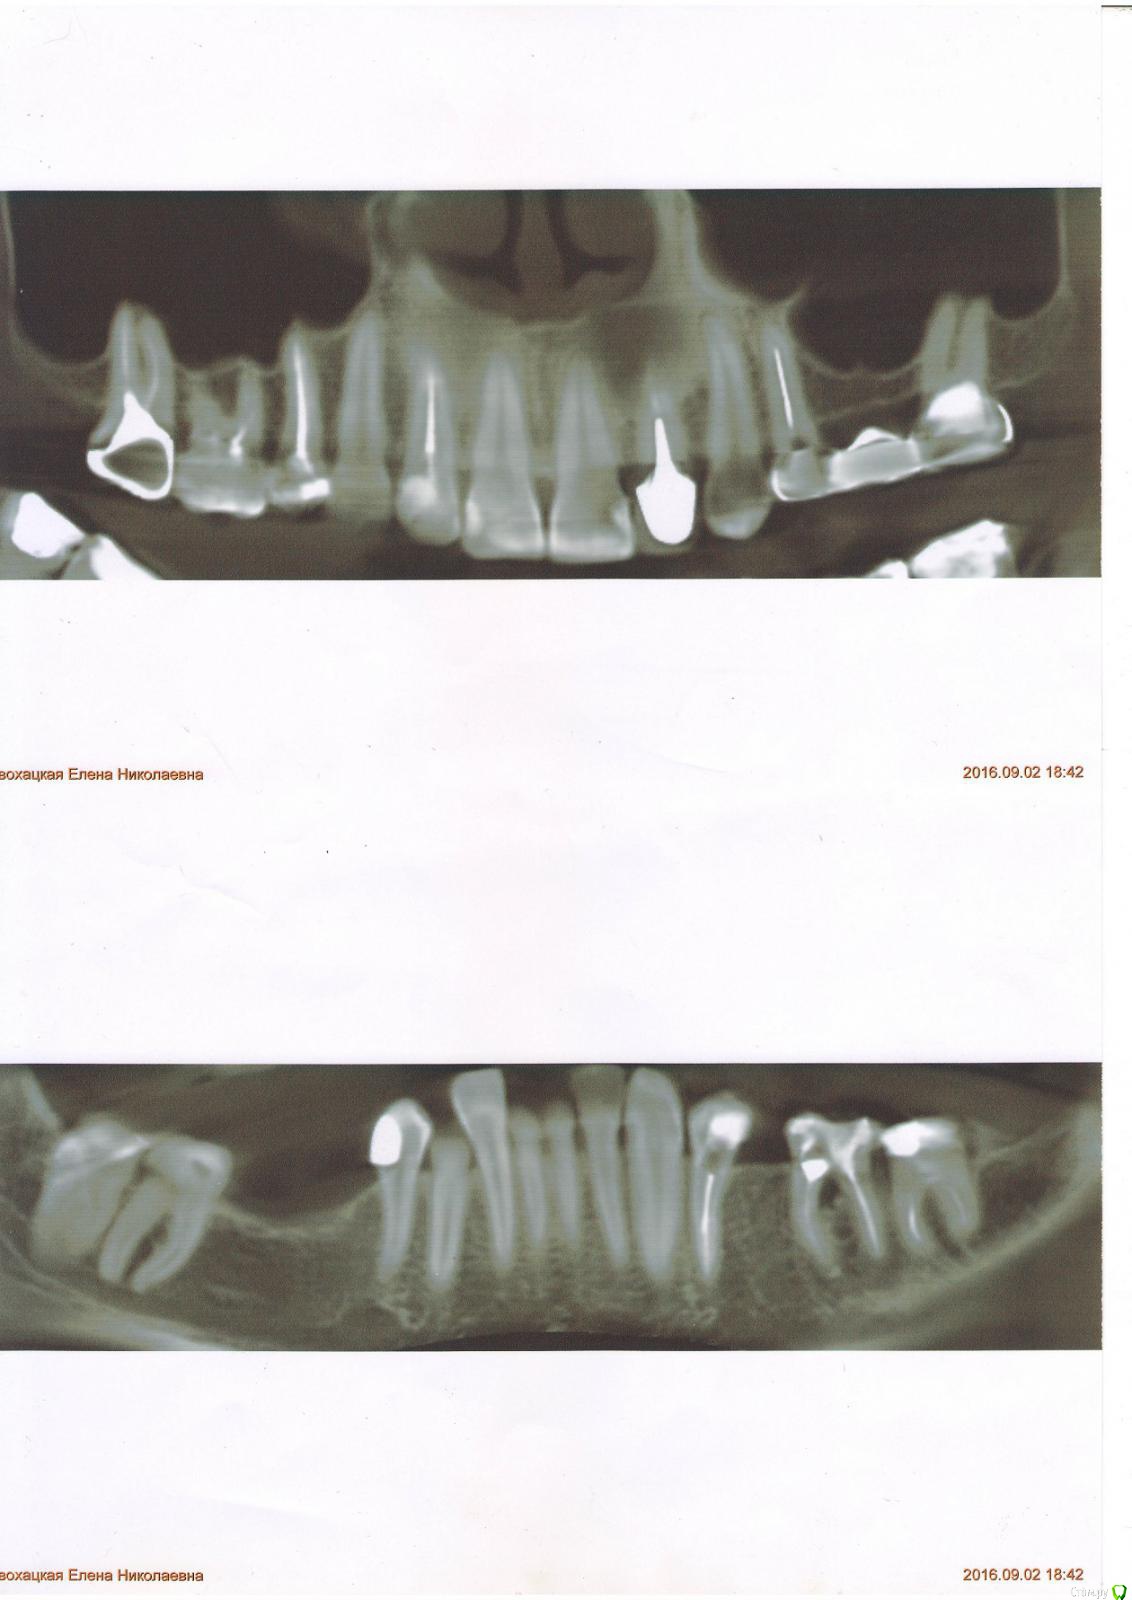

litvinenko1976 Опубликовано 29 января, 2017 Поделиться Опубликовано 29 января, 2017 Добрый день! Подскажите пожалуйста можно ли спасти зуб? В 37 зубе свищ. Первый раз образовался в 2010 году после лечения. Позже в 210 году был у другого врача был перелечен один канал, свищ почти прошел, не беспокоил. Примерно полтора гола назад образовался снова. Врач не перелечивает, говорит если будет беспокоить – удаление. Самый важный вопрос - Можно ли вылечить этот зуб? В 37 зубе свищ. Первый раз образовался в 2010 году после лечения. Позже в 210 году была у другого врача был перелечен один канал, свищ почти прошел, не беспокоил. Примерно полтора гола назад образовался снова. Врач не перелечивает, говорит если будет беспокоить – удаление. Самый важный вопрос - Можно ли вылечить этот зуб? Если да, то к какому врачу в Саратове можно обратиться? Ссылка на комментарий

Доктор Добрых Дел Опубликовано 29 января, 2017 Поделиться Опубликовано 29 января, 2017 Здравствуйте, дело не в каналах. Проблема в том, что есть воспаление между корнями. Причина скорее всего в трещине на дне полости (под пломбой). Либо перфорация. Перелечить и сохранить не удастся. Здесь показания к удалению и имплантации. 1 Ссылка на комментарий